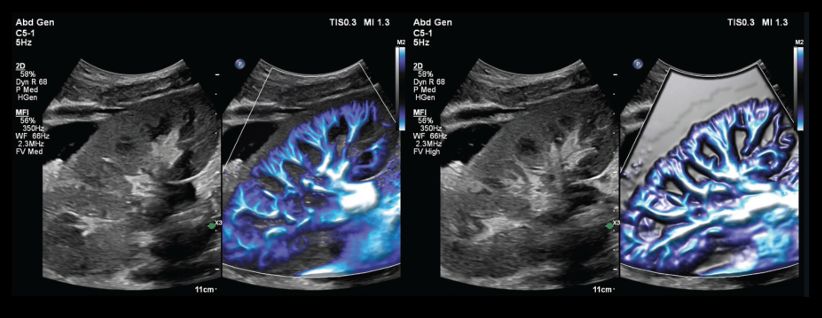

Microvascular imaging

Flow Viewer enhances MicroFlow Imaging (MFI) by improving sensitivity to small vessels.

Left: MFI frame from a renal scan, with Flow Viewer turned on and blending between the MFI and B-mode data. Right: Different MFI frame from the same renal scan, with Flow Viewer again turned on but without blending between the MFI and B-mode data (solid MFI background).

The example of renal imaging highlights how Flow Viewer increases the visibility of fine vascular structures, especially when using a solid background to emphasize flow signals.